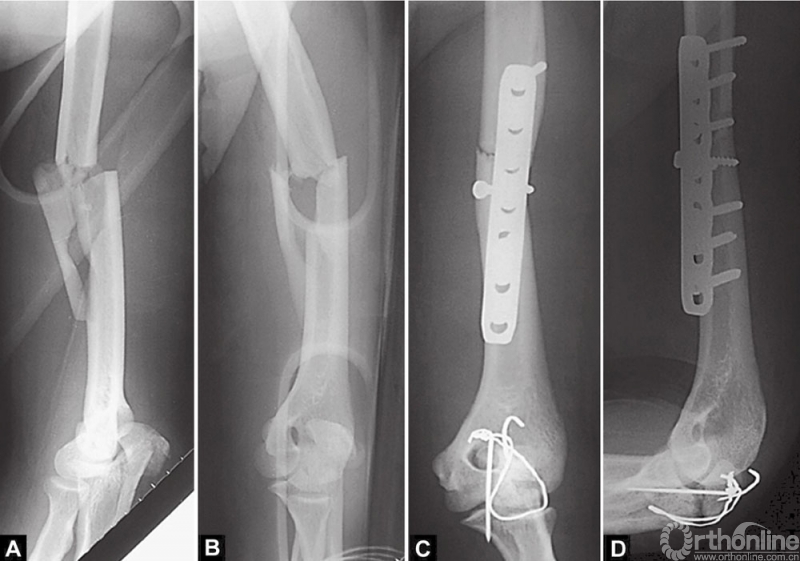

暴露骨折部位。一些外科医生更喜欢通过后侧切口暴露,患者仰卧,患肢放置在腹部。虽然这种体位方便使用C臂机在术中检查和同时进行其他肢体的手术,但除非最有经验的外科医生,这种体位并不值得提倡,因为它很难确定正确的解剖位置(图4A~D)。

图4 A~D这是肱骨和尺骨鹰嘴骨折在患者仰卧位做的内固定。很明显,两个都未固定好。如果患者侧卧或者俯卧,采用后侧入路暴露、固定骨折,就容易而且效果好得多

此外,如果骨折比预期更为复杂,这种尴尬的体位将使其难以获得很好的固定效果(图5A~C)。

图5 A~C这个尺骨鹰嘴骨折是一位多发伤年轻患者多处骨折中的一处。手术在仰卧位进行,以便使其他团队可以同时进行其他部位的手术。术中X线片(A)表明,这不是一个简单的横形骨折,它可以使用钩板以获得更好的固定。然而,医生不同意在仰卧位用钩板。手术以复位、固定不充分结束,如图(B)和(C)所示

在患者存在多处骨折需要固定的情况下,往往企图在仰卧位完成所有手术操作。很多时候,这种方法使理想的固定大打折扣。在这种情况下,应该应用骨科损伤控制概念来个性化手术。每个骨折都应该得到最佳的复位和固定,以使患者所有受伤的部位重新获得最大的功能。